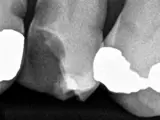

Pain is a good indicator that you may need a root canal. However, pain is not the only indicator of needing a root canal. Regular X-rays and check-ups are needed to make sure the root system of your teeth is healthy. Many times, through X-rays, we find an asymptomatic tooth that has an abscess. Also, X-rays are our only tool to discover internal resorption. The earlier this is detected, the better the prognosis is for saving the tooth with root canal therapy.